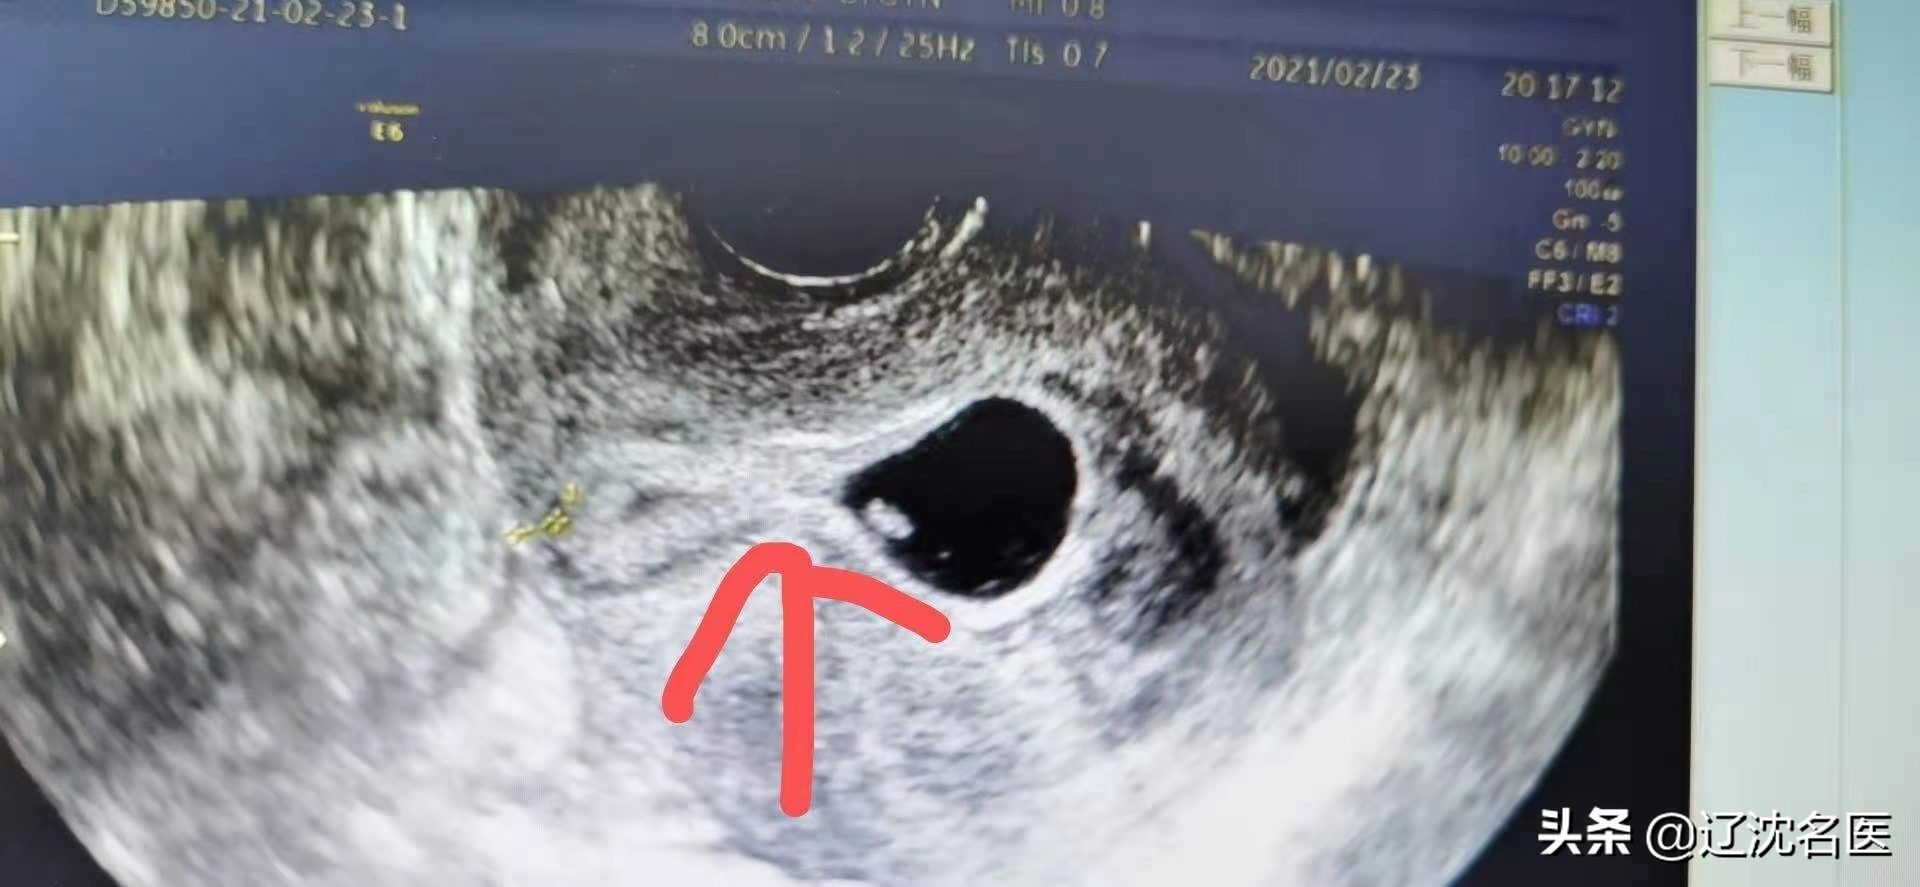

王华(化名)停经46天,伴阴道大量流血突然增多,下腹疼痛来省妇幼就诊。经急诊超声检查确认为剖宫产瘢痕部位妊娠,宫腔内还有很多积血,其妊娠囊生长在剖宫产切口憩室内,子宫前壁肌层仅剩不到1毫米,患者随时有子宫破裂大出血的危险。